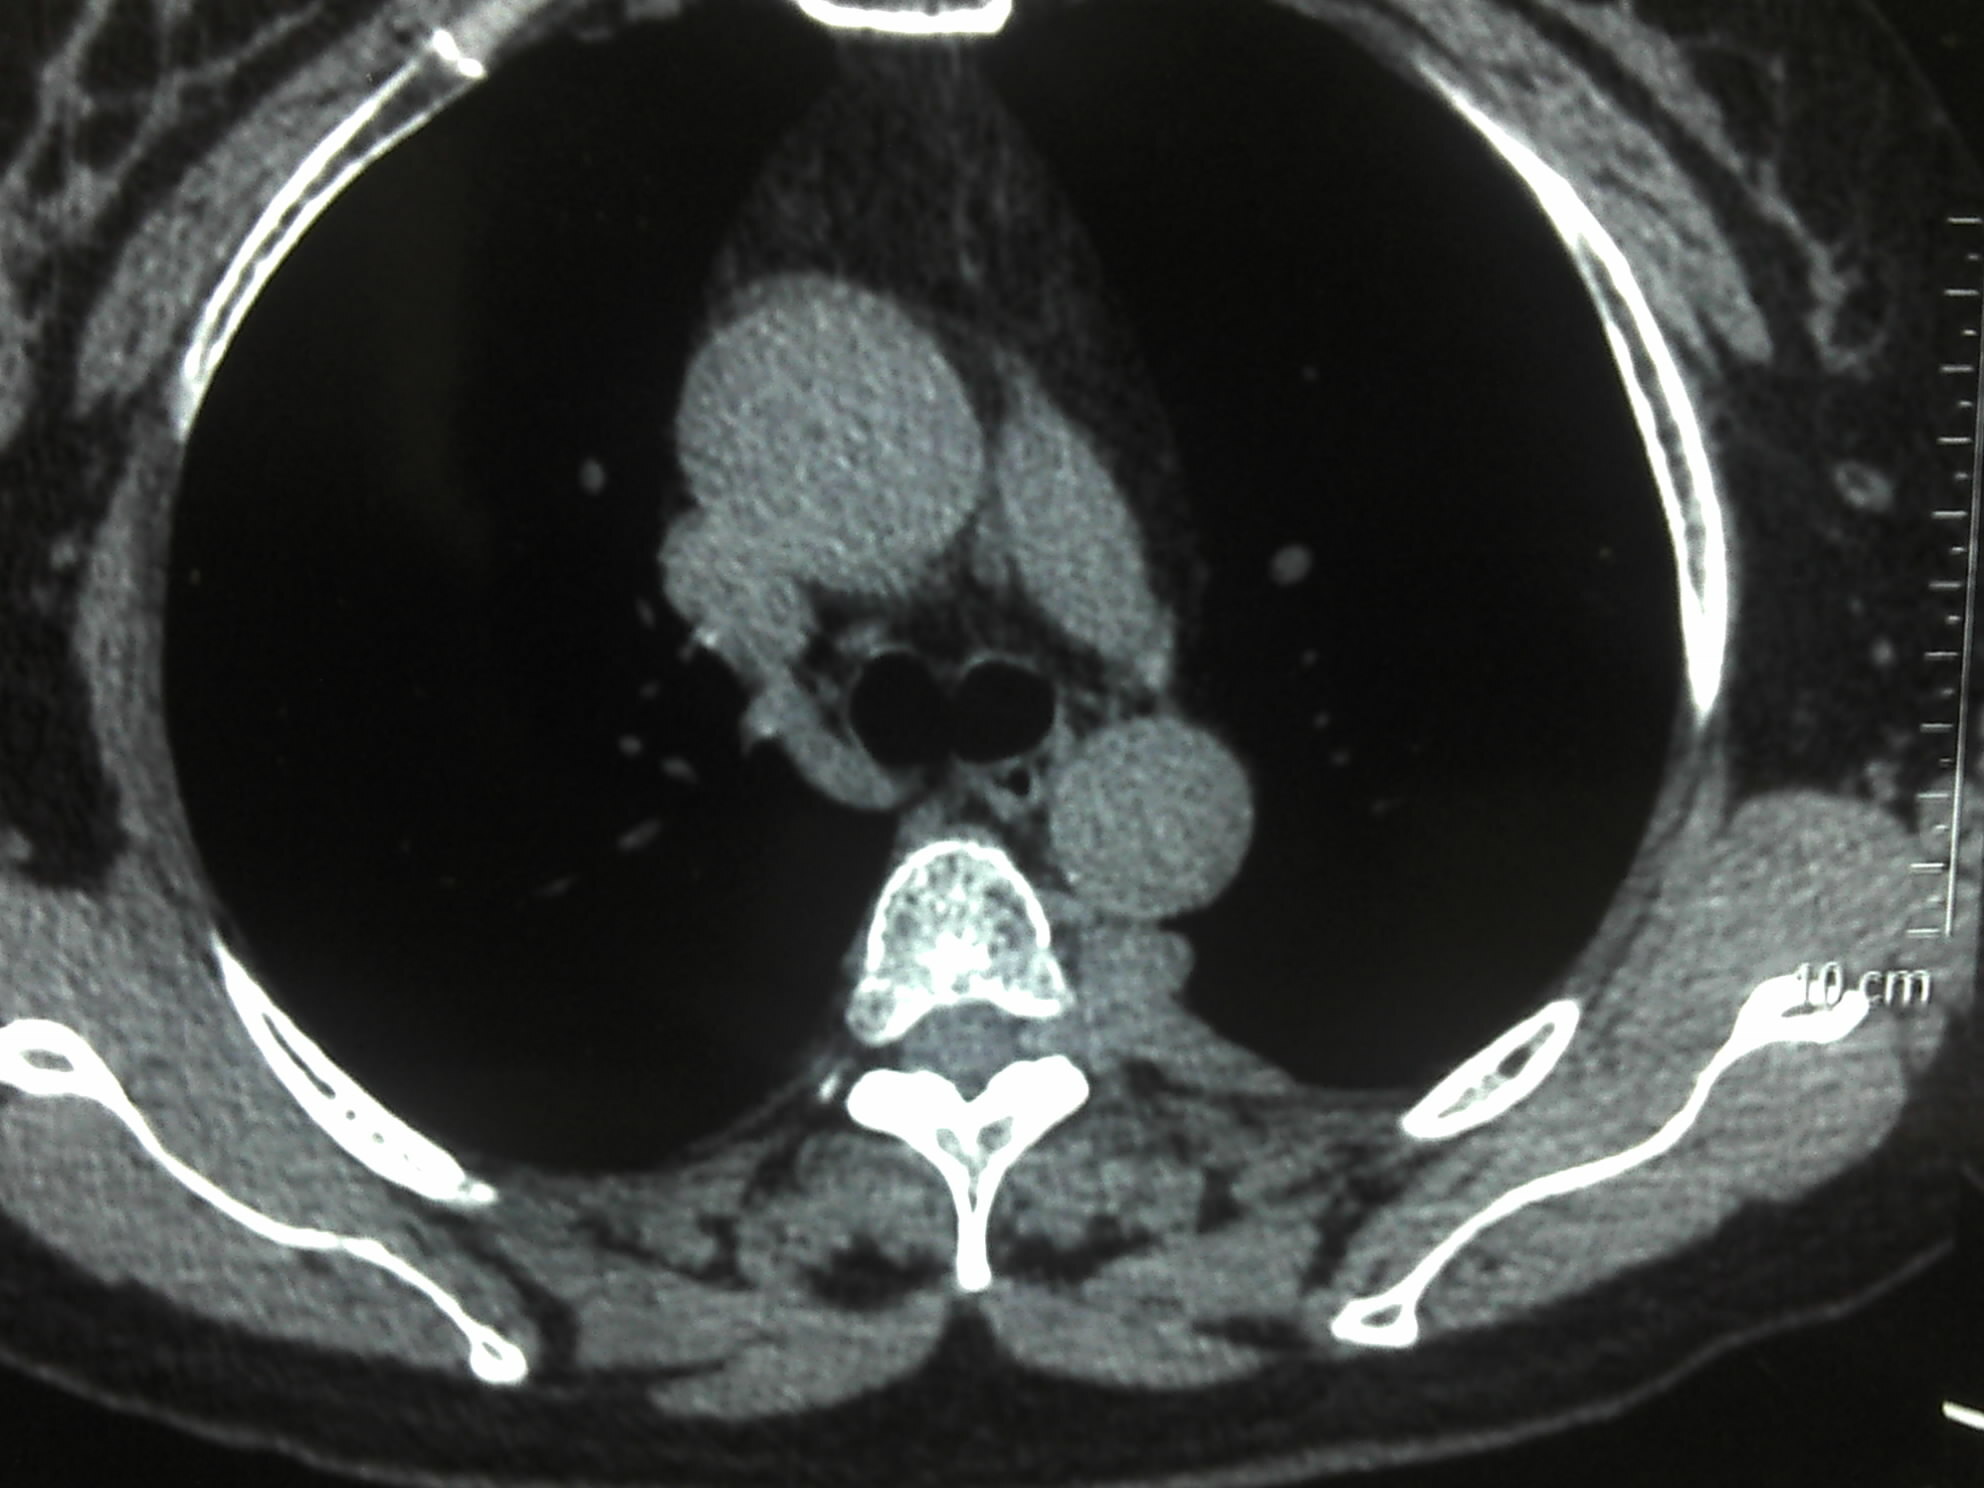

放疗疗效非常好,病人及家属非常满意,但好景不长,幸福的时光往往那是短暂的。好像没过多长时间,病人出现了双下肢无力的症状,检查脊椎核磁显示椎管内多发占位性病变,并出现了胳膊及大腿部位的多个皮下结节。

下图是患者的影像表现: